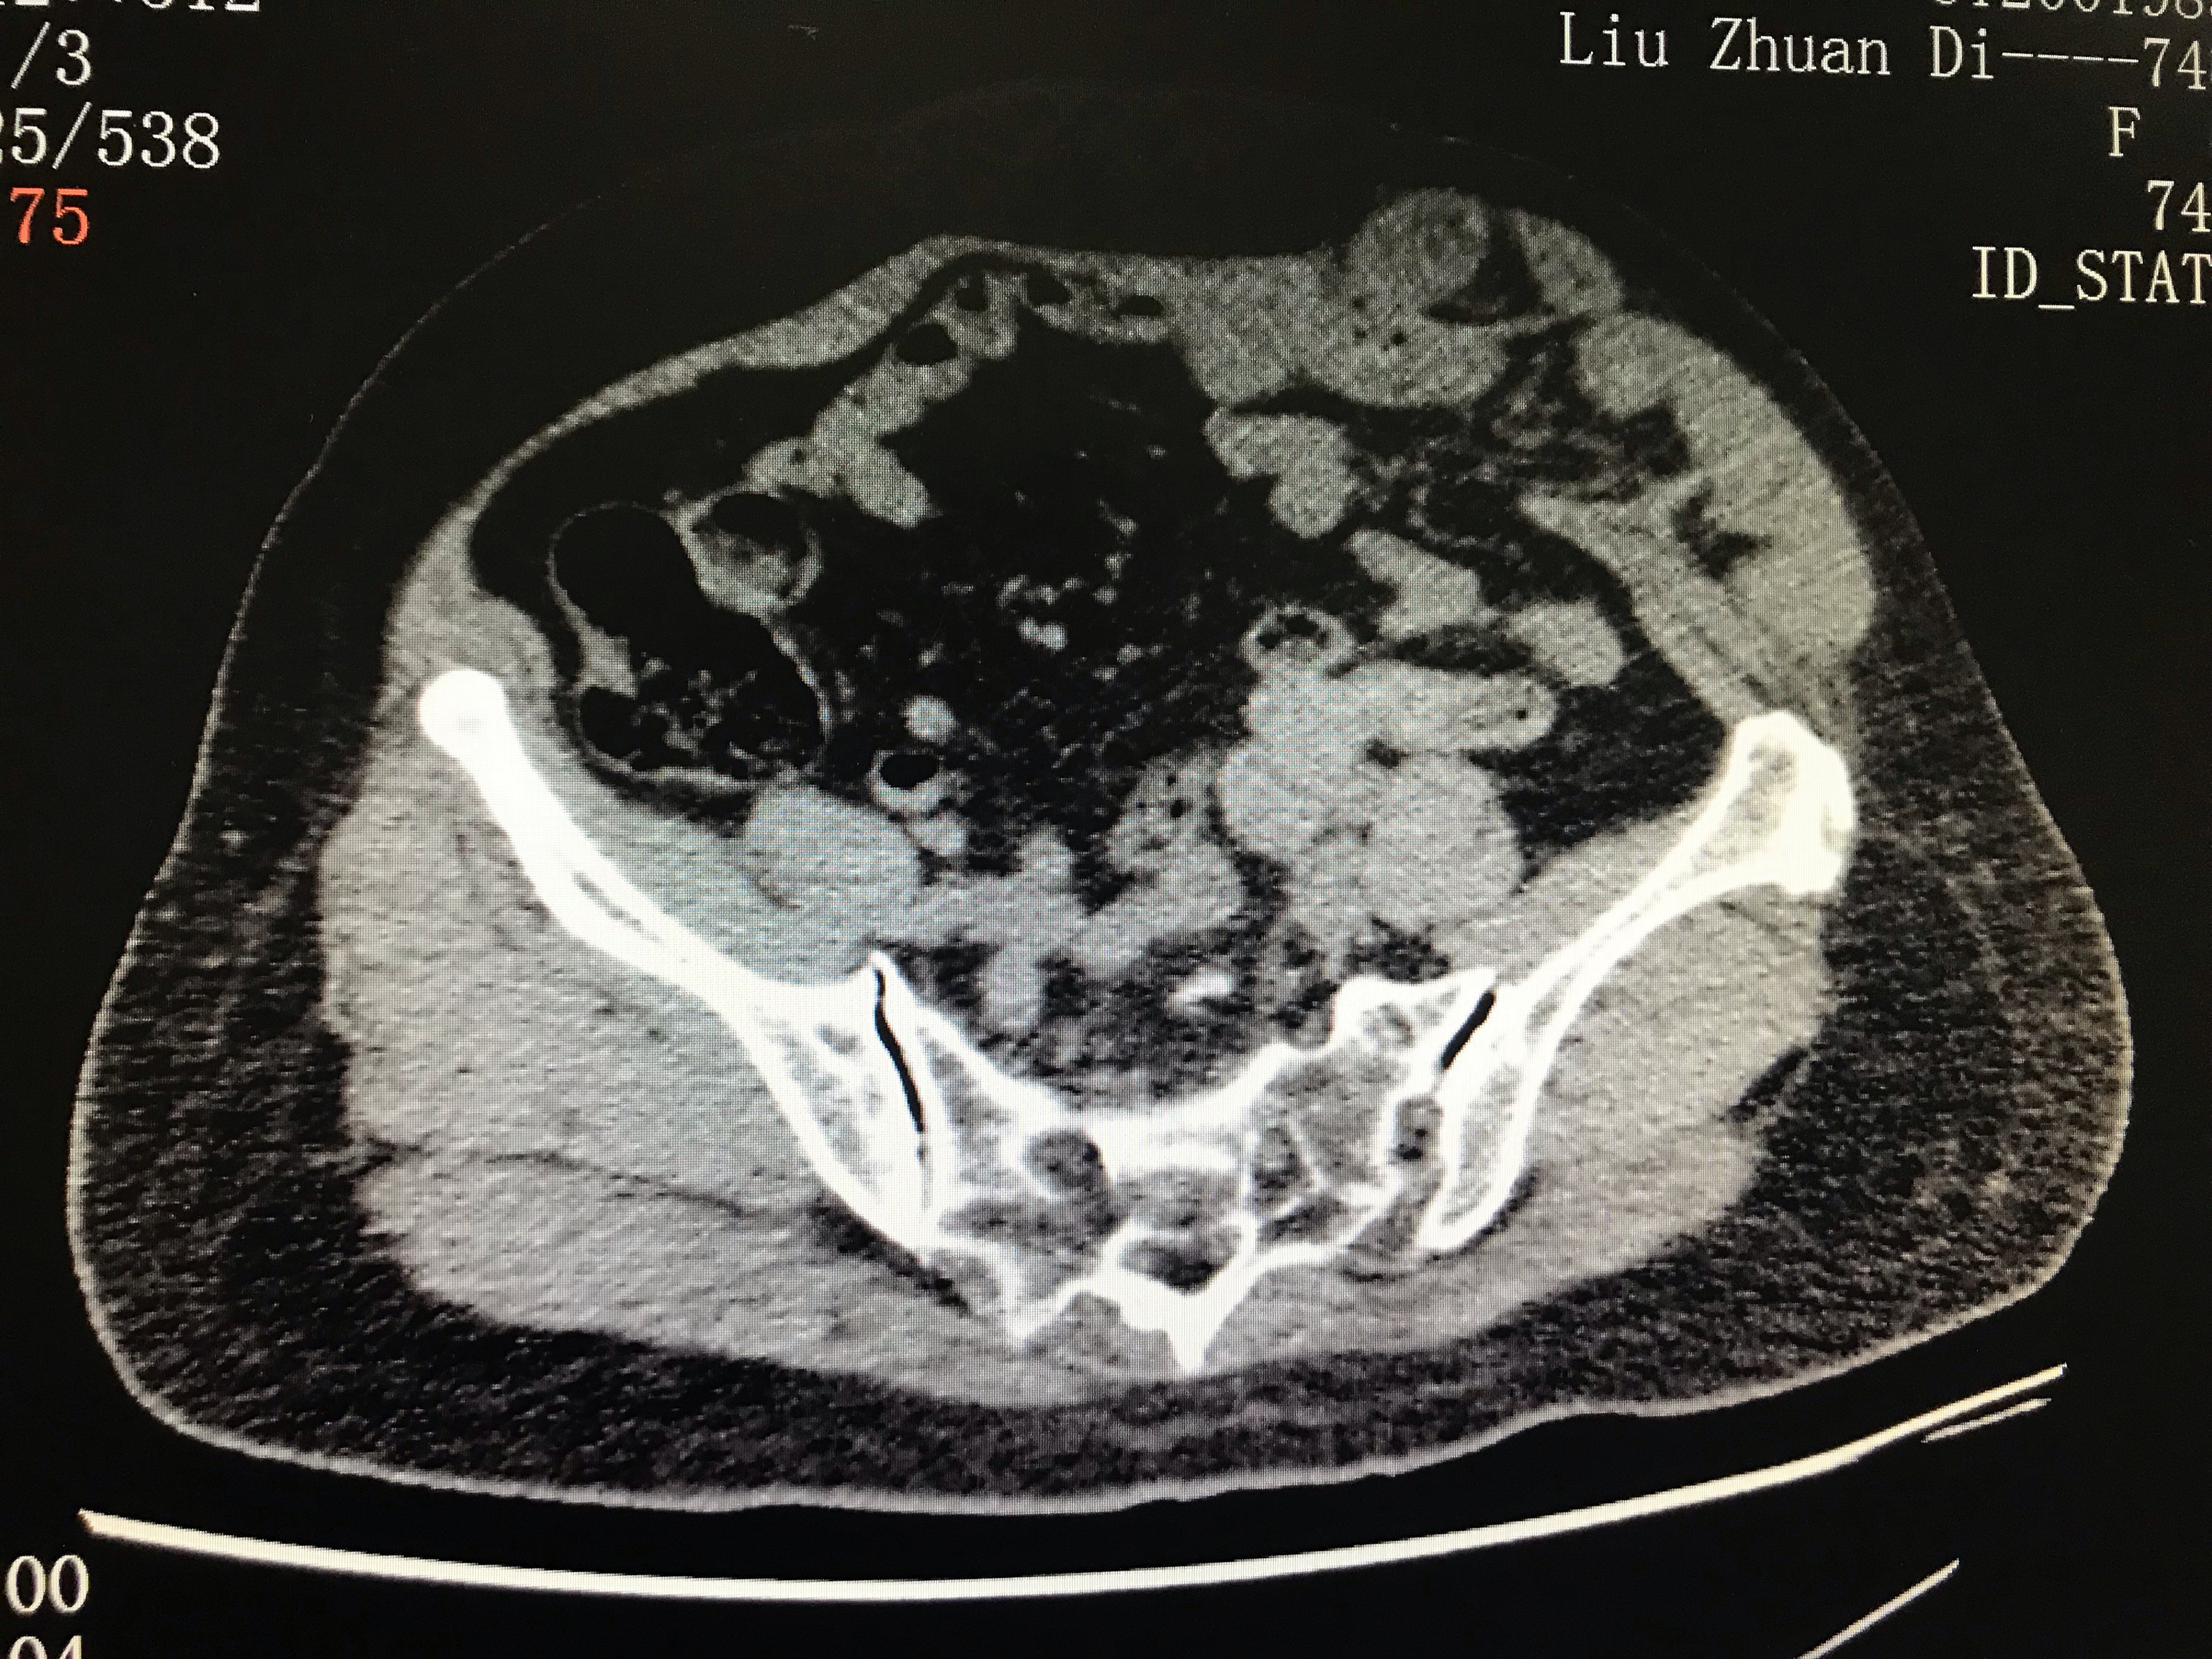

腹壁切口疝超声图片,切口疝图片

腹壁疝(体表 超声图)

切口疝图片

腹壁切口疝图片

切口疝图片腹部

腹部手术切口疝图片